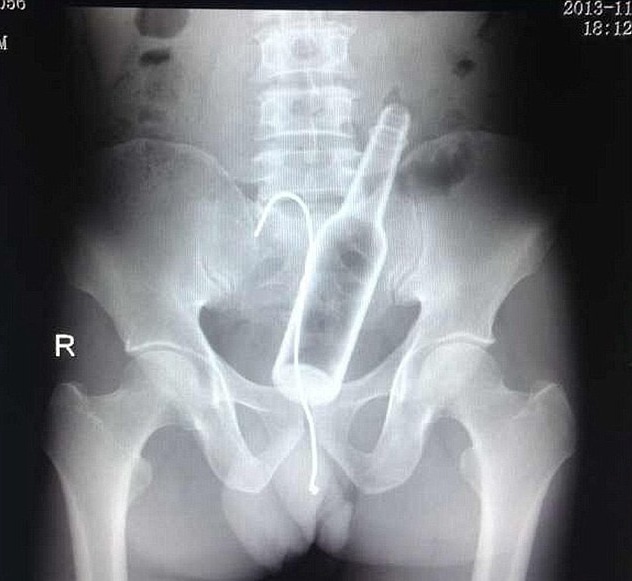

Ρεζίλι των σκυλιών έγινε ένας άντρας στο νοσοκομείο Φουτζού της επαρχίας Φουτζιάν στην Κίνα, όταν πήγε για να κάνει ακτινογραφίες και ανακάλυψαν οι γιατροί ότι είχε μπει στον πρωκτό του ένα μπουκάλι και μαζί το αγκίστρι του ψαρέματος!

Ο Κινέζος βρισκόταν στο σπίτι του και για κάποιο λόγο θέλησε να δει αν χωράει ένα μπουκάλι στον πρωκτό του και το έχωσε τόσο βαθιά που του ήταν αδύνατο να το βγάλει με το χέρι.

Έτσι, για να το τραβήξει πήρε καλάμι ψαρέματος, έβαλε το αγκίστρι του στο μπουκάλι που ήταν μέσα του και άρχισε να τραβάει. Όμως, δεν τα κατάφερε και αναγκάστηκε να ζητήσει βοήθεια από γιατρούς, οι οποίοι έμειναν άναυδοι όταν αντίκρυσαν τις ακτινογραφίες. Τελικά, μετά από εγχείρηση κατάφεραν να εξάγουν όλα τα αντικείμενα που είχαν χωθεί εκεί μέσα!